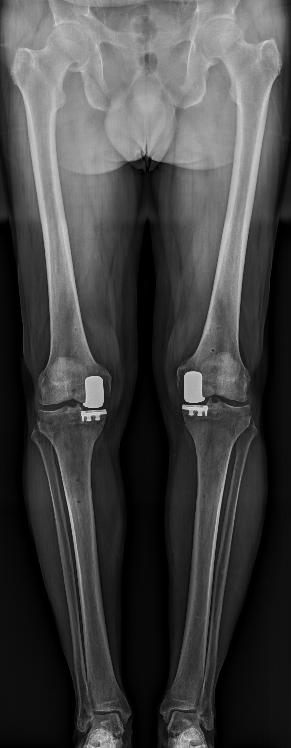

La PUC est indiquée en cas d’arthrose fémoro-tibiale interne / externe localisée ou d’atteinte femoro-patellaire isolée. Cette chirurgie peut être nécessaire en cas de douleur, d’impotence fonctionnelle et en cas d’échec du traitement médical. Le traitement médical associe des règles Hygiéno-Diététiques, avec, selon les cas : une rééducation spécifique, des antalgiques, des anti-inflammatoires, des infiltrations intra articulaires.